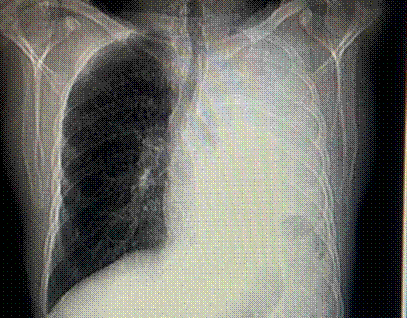

Inicia su padecimiento en octubre de 2014, de manera insidiosa con tos productiva, acompañada de expectoración blanquecina, sin predominio de horario. La tos se intensificó durante el día y ocasionalmente interrumpió el sueño nocturno. Una semana después aparecieron episodios esporádicos de hemoptisis, descritos como expulsión de pequeñas cantidades de sangre fresca mezclada con expectoración. Estos síntomas se acompañan de fiebre de predominio vespertino, escalofríos ocasionales y sudoración profusa nocturna. De forma paralela, presentó astenia, adinamia, hiporexia y pérdida de peso no intencionada de aproximadamente 7 kg en pocas semanas. Agregándose dolor torácico infraclavicular derecho, exacerbado por inspiración profunda y la tos, sin alivio significativo con el reposo o analgésicos. Persistieron la tos, la disnea leve a esfuerzos moderados y los episodios ocasionales de hemoptisis, motivo por el cual acudió a valoración médica. Sin antecedentes personales de enfermedades respiratorias crónicas o contacto con personas con tuberculosis ni viajes recientes, se decidió su hospitalización para protocolo de estudio. Realizándose de manera inicial tomografía axial computarizada (TAC) de tórax inicial, la cual reveló una imagen sugestiva de proceso neoplásico en el lóbulo superior pulmonar izquierdo. Posteriormente, en noviembre de 2014 se efectuó broncoscopia diagnóstica, evidenciándose una lesión tumoral endobronquial de la cual se tomaron biopsias dirigidas, cuyo resultado fue neoplasia maligna epitelial de alto grado, ulcerada y necrosada, del tipo células aveniformes. El 8 de diciembre de 2014, un nuevo estudio anatomopatológico confirmó la presencia de neoplasia maligna poco diferenciada, compatible con carcinoma de células pequeñas de pulmón, con abundante necrosis y una reacción linfocítica prominente. El 17 de febrero de 2015, una nueva TAC de tórax realizada en el Hospital General de Zona No. 1 mostró opacificación total del parénquima pulmonar izquierdo, compatible con progresión neoplásica (Figura 1), así como múltiples lesiones micronodulares de distribución intersticial en el pulmón derecho, sugestivas de linfangitis carcinomatosa (Figura 2). Los hallazgos radiológicos fueron además compatibles con neumoconiosis silicótica. Confirmado el diagnóstico, el paciente fue referido al servicio de Oncología, donde inició tratamiento especializado con radioterapia. La evolución radiológica evidenció progresión tumoral y compromiso bilateral con patrón micronodular difuso.

Figura 1.

Tomografía axial computada, corte axial.

Nota: Hemitórax izquierdo ocupado por derrame pleural, con desplazamiento contralateral de estructuras mediastínicas. En parénquima derecho se observa patrón micro nodular difuso peri hiliar, característico en neumoconiosis en etapa avanzada.

El paciente presentó una exposición ocupacional prolongada de 29 años a polvo de sílice cristalina respirable, sin uso adecuado uso del sistema de gestión de riesgos, desarrollando neumoconiosis por sílice y posteriormente carcinoma pulmonar de células pequeñas. Los estudios de imagen iniciales evidenciaron una opacidad total del pulmón izquierdo acompañada de lesiones micronodulares en el pulmón derecho, signos radiológicos compatibles con neumoconiosis. El diagnóstico por medio de anatomía patológica confirmó, mediante biopsia bronquial, una neoplasia maligna epitelial de alto grado, variedad células aveniformes, con abundante necrosis y reacción linfocítica prominente.